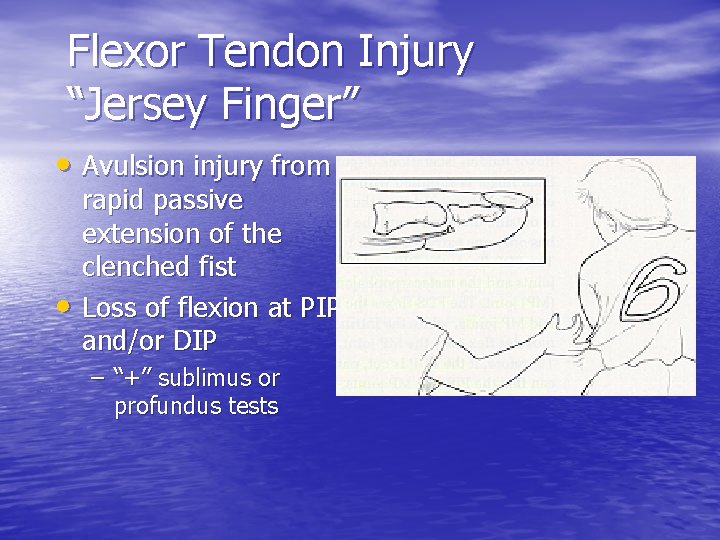

Flexor Tendon Injury “Jersey Finger” • Avulsion injury from • rapid passive extension of the clenched fist Loss of flexion at PIP and/or DIP – “+” sublimus or profundus tests